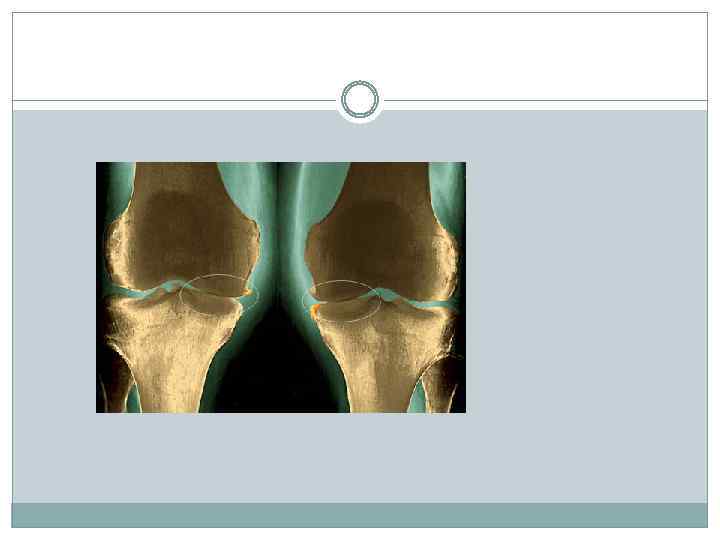

Деформирующий артроз Деформирующий артроз – хроническое заболевание сустава, которое является следствием однократной тяжелой внутрисуставной травмы или инфекционного артрита, или длительной работы, связанной с микротравматизацией или перенапряжением сустава. Профессиональный артроз наблюдается обычно в молодом или среднем возрасте. Наиболее часто поражаются суставы кисти при работе, требующей систематического напряжения кистей, выполняемой в быстром темпе и сопровождающейся травматизацией суставов (сапожники, кузнецы). Артроз крупных суставов чаще встречается у людей, выполняющих тяжелую работу (горнорабочие, каменщики). На рентгенограмме заметно сужение суставной щели, уплощение головки и суставной впадины, по краям суставных поверхностей видны костные разрастания.